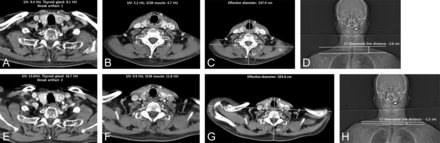

Representative neck CT images obtained with the intervention (A–D) and standard (E–H) protocols. The images demonstrate the measurements for image noise at the lower neck (first costovertebral joint level, A and E) and midneck (cricoid cartilage level, B and F), and the effective diameter measurement at the midneck (C and G). The C7-biacromial line distance was determined as illustrated on images D and H. The white line indicates the biacromial line; arrow, the C7-biacromial line distance; SCM, sternocleidomastoid; IJV, internal jugular vein; HU, Hounsfield units.

One neuroradiologist with 7 years of dedicated head and neck experience assessed the image noise by calculating the SD of the CT values in Hounsfield units for pixels within an ROI fitted within the relevant structures (as outlined below). CT values were measured at the mid- and lower neck levels contralateral to the side used for the intravenous contrast media administration. The ROIs were placed on the internal jugular vein and sternocleidomastoid muscle at the level of the cricoid cartilage (midneck) and the thyroid gland and internal jugular vein at the level of the first costovertebral joint (lower neck).

For the evaluation of streak artifacts, 2 board-certified neuroradiologists with 15 and 8 years of experience independently analyzed the axial CT images on a PACS screen, with the scanning parameters removed from the screen to blind the reviewers to whether the arm traction device was being used. All image assessment was performed with a standard soft-tissue setting (window width: 300/window level: 35). The degree of streak artifacts in the supraclavicular fossa was evaluated and scored as follows: 1, no or minimal artifacts with no image obscuration; 2, mild artifacts causing partial obscuration of subcutaneous fat or skin without diagnostic interference; and 3, severe artifacts causing obscuration of deep cervical structures with diagnostic interference.9 The supraclavicular fossa was defined on each axial scan when any portion of the clavicle was identified on 1 side of the neck.12

Radiation exposure was evaluated with DLP and CTDIvol. Potential confounds, including the effective diameter of the neck and the z-axis scan range, were also assessed. The effective diameter of the neck was calculated from an axial CT image at the level of the lower margin of the cricoid cartilage using the following equation: Effective Diameter = √Anteroposterior Diameter × Transverse Diameter.13 The total scan length was assessed for each patient by multiplying the total number of axial images acquired by the section thickness. To measure the degree of shoulder-level shift, we determined the C7-biacromial line distance. Two straight lines were drawn on the anteroposterior scout image: One was the line connecting the upper margin of the shoulder acromion bilaterally (biacromial line),14 while the other line was parallel to the middle of the upper endplate of C7. The C7-biacromial line distance was defined as the distance between the 2 straight lines (Fig 2). The measurement was expressed as negative if the biacromial line was located caudal to the upper margin of C7 and positive if the line was located cranial to the upper margin of C7.